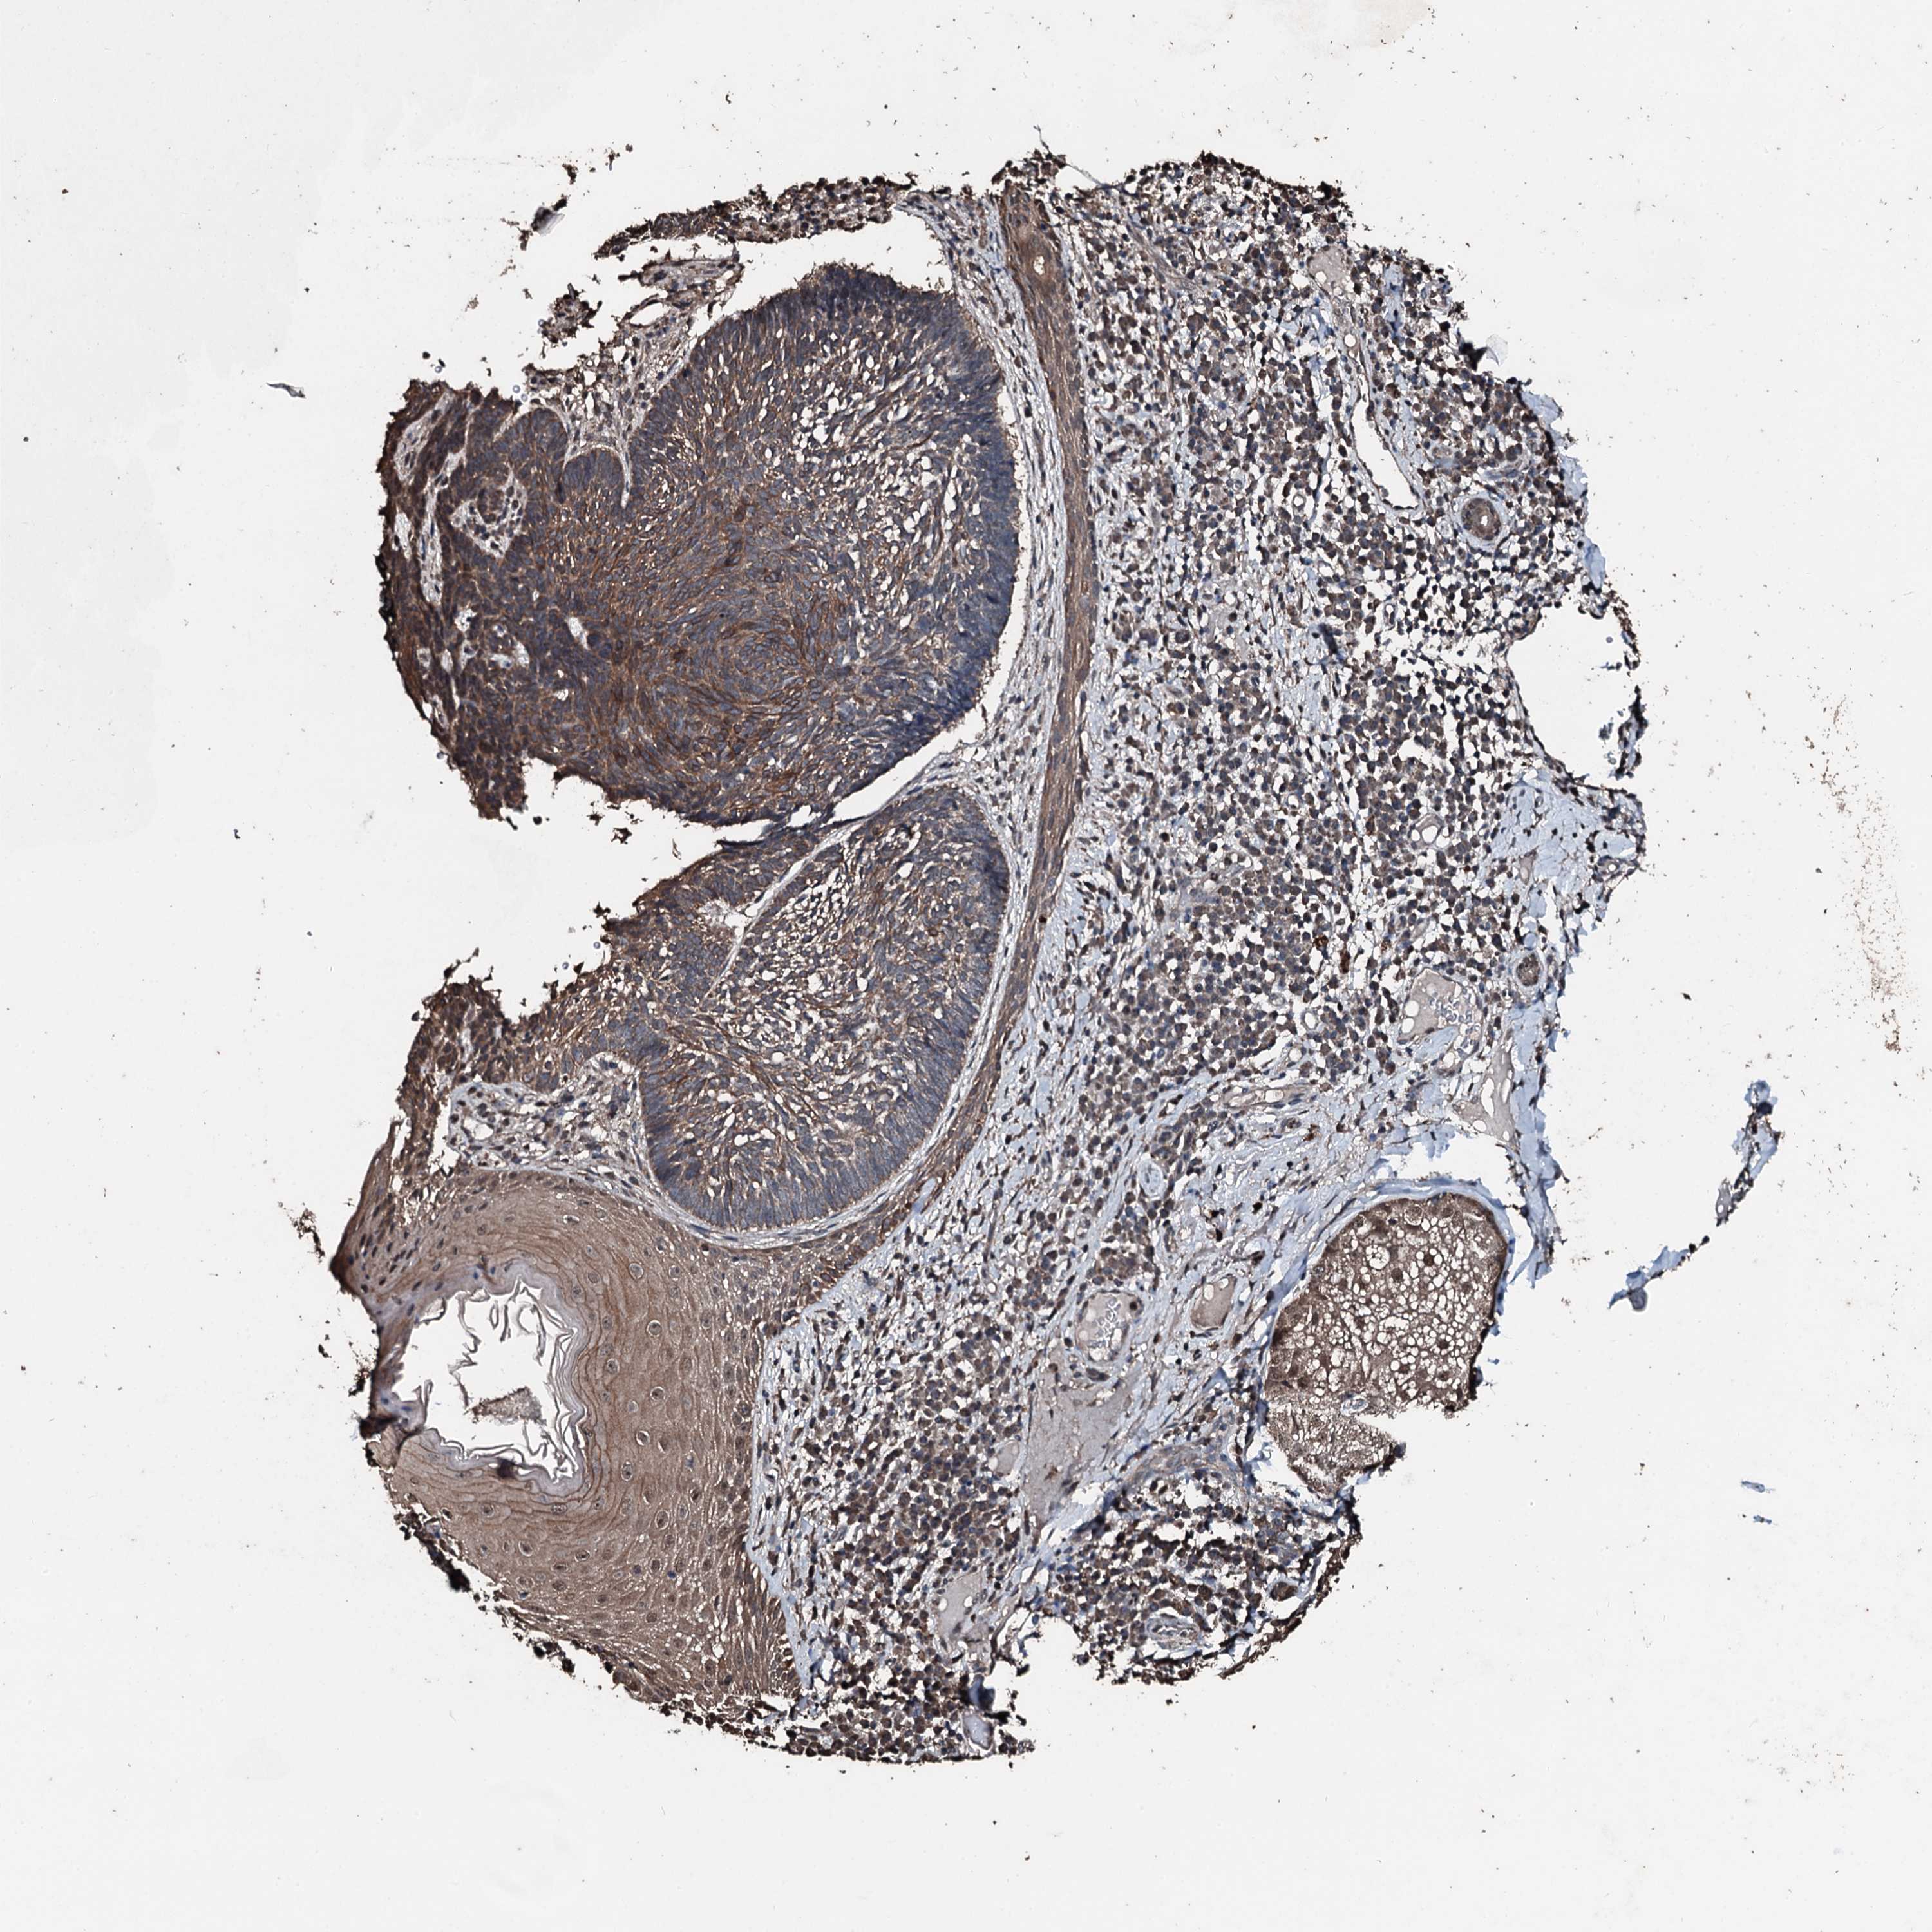

SKIN CANCER - Protein expressioni

A mouse-over function shows sample information and annotation data. Click on an image to view it in a full screen mode. Samples can be filtered based on level of antibody staining by selecting one or several of the following categories: high, medium, low and not detected. The assay and annotation is described here.

Antibody staining in the annotated cell types in the current human tissue is reported as not detected, low, medium, or high, based on conventional immunohistochemistry profiling in selected tissues. This score is based on the combination of the staining intensity and fraction of stained cells.

Each image is clickable and will lead to virtual microscopy that enables deeper exploration of all samples and also displays staining intensity scores, fraction scores and subcellular localization as well as patient and tissue information for each sample.

Antibody HPA041168

Squamous cell carcinoma, NOS

Squamous cell carcinoma, metastatic, NOS